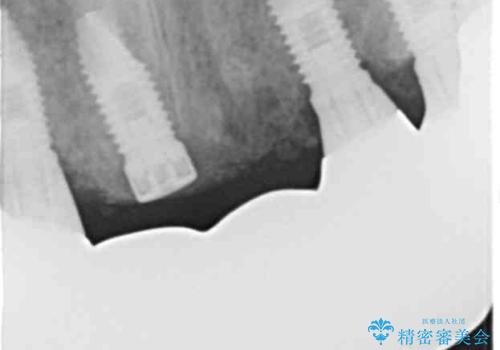

治療途中で患者様が喫煙を再開され、最もタバコの影響を受けやすい上顎前歯部(右上31)インプラント周囲の骨吸収と少量の排膿を認めました。

長期的予後不良と判断した右上3フィクスチャーを除去し、人工骨による骨増生及び右上2に埋入を行いました。

保存可能な右上1のフィクスチャーは粘膜下にスリープさせ、左上2の埋入を行いました。